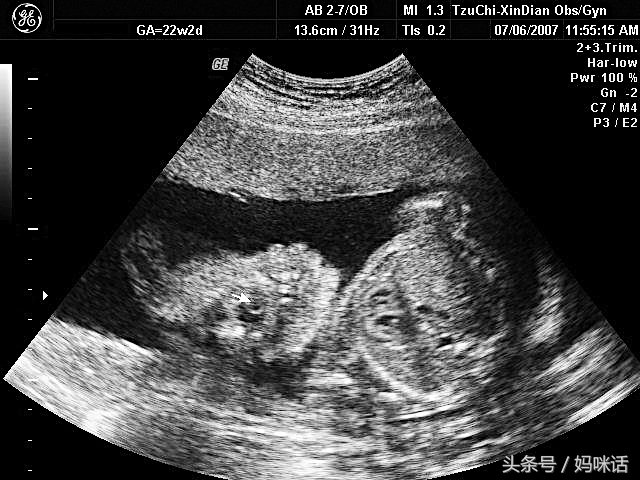

最后一张(第四张),包在宝宝外面黑黑的一片就是羊水,而上方一大片白白的就是胎盘。